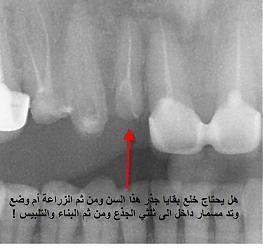

بالنسبة لحالتك أنت تحتاج لأكثر من ثمانية تلبيسات كما اشاهد من الصورة

ولكن كما أشاهد في الصورة يوجد لديك مشكلة في أحد الأسنان وهو الناب الموجدود جانب السن المكسور ( والذي لا أظن أنه بحاجة إلى قلع ) سنكشف عليه عندما تأتي إلى العيادة

في حالة خلع ماتبقى من جذع سن الرباع هل تتم الزراعة بعد الخلع مباشرة والتعويض النهائي ام يحتاج لفترة شهر على الاقل قبل وضع الزرعة وما مدى نجاح الزراعة بعد الخلع مباشرة

لا يوجد مشكلة من الزرع المباشر بعد القلع على شرط أن لا يكون السن أو الضرس فيه أي خراج أو فيه قيح ، أما موضوع التعويض فهو لا يتم بشكل فوري وإنما يجب الأنتظار أربع أشهر ويمكن أن يكون أكثر من أربع أشهر إذا كان الوقت غيرمناسب لإتمام الزراعة